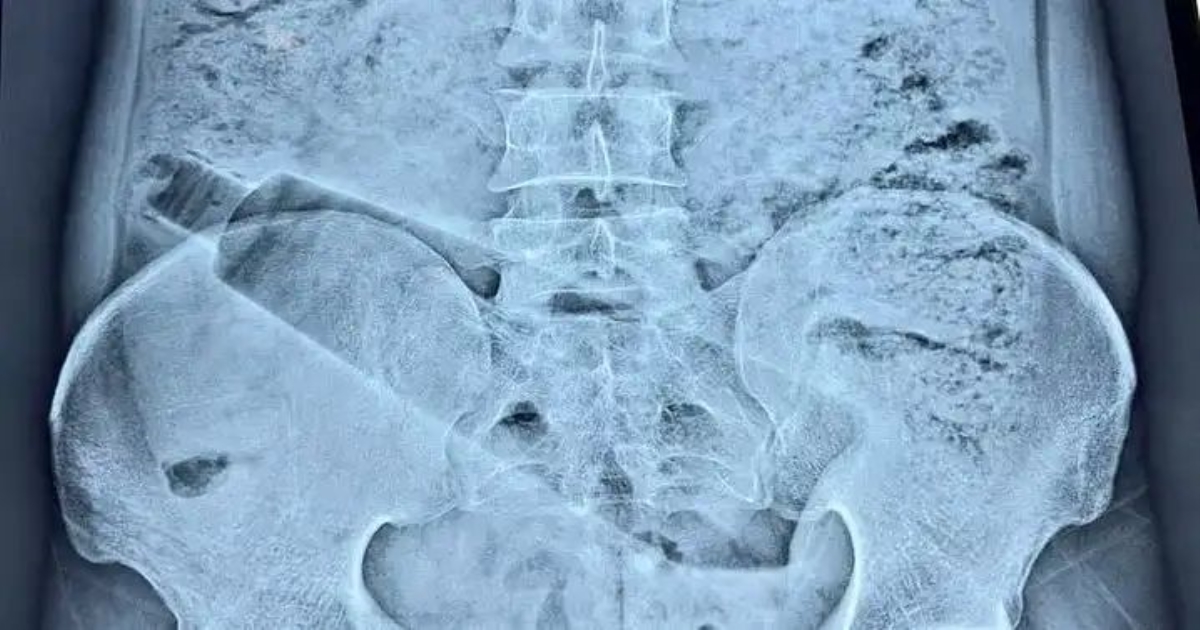

உத்தரப்பிரதேசத்தைச் சேர்ந்த ஒரு வாலிபர், அகமதாபாத் அம்பேத்கர் நகர் பகுதியில் வசித்து வந்த நிலையில், எதிர்பாராத விதமாக அவரது மலக்குடல் பகுதியில் ஒரு பிளாஸ்டிக் பாட்டில் சிக்கிக்கொண்டது. இதனால் கடுமையான வயிற்று வலியால் அவதிப்பட்ட அவர், உடனடியாக மருத்துவமனைக்கு கொண்டு செல்லப்பட்டார். பரிசோதனையில் அவரது உடலில் பாட்டில் இருப்பது உறுதி செய்யப்பட்டதால், மருத்துவர்கள் அதிர்ச்சியடைந்தனர்.

நிலைமை மோசமாக இருப்பதை உணர்ந்த மருத்துவர்கள் குழு, உடனடியாக அவசர அறுவை சிகிச்சை மேற்கொள்ள முடிவு செய்தனர். சுமார் 70 நிமிடங்கள் நீடித்த சிக்கலான அறுவை சிகிச்சையின் மூலம், அந்த பாட்டிலை வெற்றிகரமாக அகற்றினர். தற்போது அந்த நபர் தீவிர கண்காணிப்பில் சிகிச்சை பெற்று வருகிறார்.